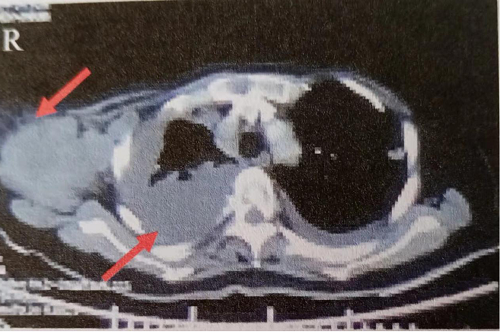

治疗:先后予替莫唑胺+奈达铂方案化疗及恩度治疗3周期,治疗效果明显,右侧胸腔积液基本消失,右腋窝淋巴结明显缩小(图2)。

图2 胸部CT示右侧胸腔积液基本消失,右侧腋窝淋巴结缩小至3.6cmx1.8cm